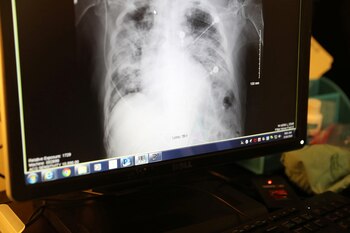

El nuevo coronavirus podría haber llegado al Viejo Continente en noviembre de 2019, según revelaciones de científicos franceses. El doctor Michel Schmitt, del Hospital Albert Schweitzer en Colmar, noreste de Francia, examinó junto a su equipo de investigadores miles de radiografías de tórax a fines de 2019. Pudieron identificar dos escáneres que eran consistentes con los síntomas de COVID-19, la enfermedad causada por el virus SARS-CoV-2 que registra más de 6.1 millones de casos confirmados en todo el mundo, según la Universidad Johns Hopkins.

Los escaneos, que fueron obtenidos por NBC News, se encontraban entre los casi 2.500 rayos X que el equipo de Schmitt analizó y muestran que el virus estaba en el país antes de su primer caso reportado el 24 de enero. El 13 de enero, la OMS confirmó el primer caso fuera de China localizado en Tailandia.

El neumólogo y experto en salud global de la Universidad de Washington, doctor Vin Gupta, quien analizó los rayos X, dijo a NBC News: “Esto se ajusta a un patrón que estamos viendo con el coronavirus, especialmente la infección temprana por coronavirus donde se observan algunas anormalidades en algunos partes de los pulmones pero no anormalidades en todas partes”. El equipo del doctor Schmitt también pudo identificar 12 casos de coronavirus en diciembre y 16 en enero.